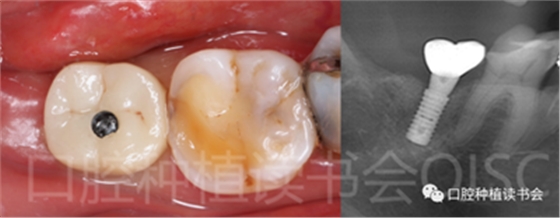

5.3.3 根據(jù)拔牙窩內(nèi)的牙槽間隔高度,植入康盛CANSUN柱形親水種植體(4.3*8mm),確保種植體肩臺與牙槽間隔平齊,種植體的所有表面均被自體骨包繞(圖16),植入扭矩為25N.cm。

圖16 盡量讓種植體表面被牙槽間隔的自體骨包繞。

5.3.6 術后即刻CBCT(美亞光電)檢查種植體軸向及深度良好(圖19)。

圖19 術后即刻CBCT確認種植體頰、

舌側(cè)骨板完整,并保持了足夠的厚度。

5.4.3 術后第10周,47戴入最終種植冠,X片確認基臺就位準確(圖25),以30N.cm扭矩旋緊基臺螺絲(圖26)。

5.4.4 種植冠封閉螺絲孔后,調(diào)合,拋光,完成最終修復(圖27);戴牙前CBCT顯示:種植體頰側(cè)骨板厚度為2.88mm;47種植冠獲得了良好的穿齦輪廓,并維持了正常的頰側(cè)牙弓輪廓。